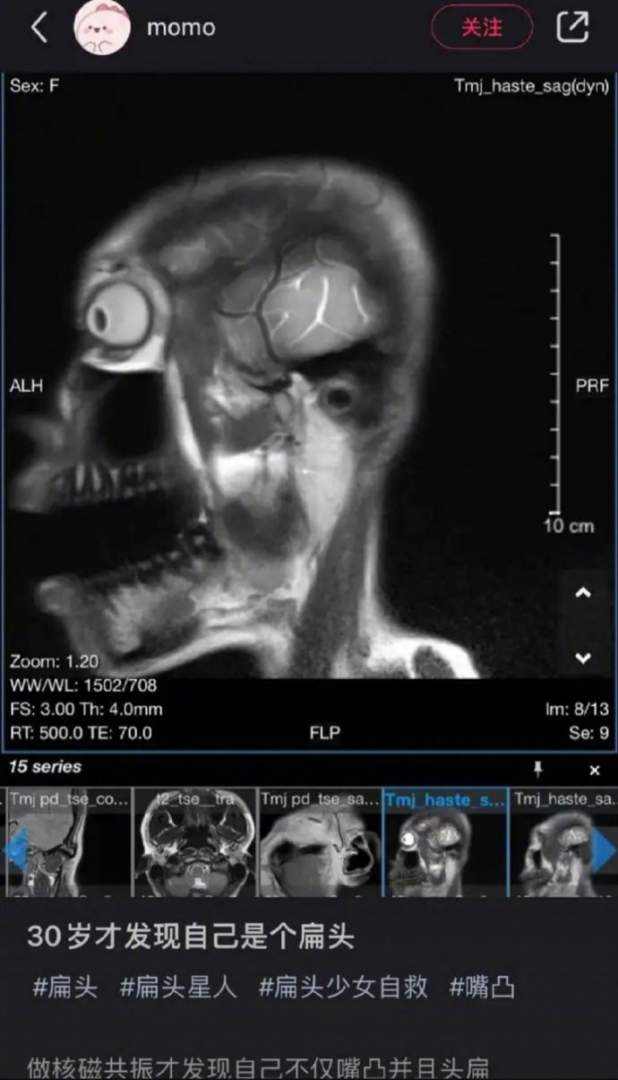

事情好像不是头扁这么简单。

PS:猜您姓辛普森吧。